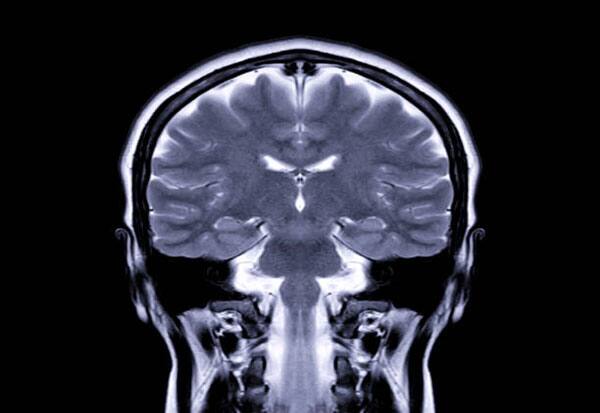

New Delhi: A "single five-minute" brain scan could help predict individuals at risk of experiencing psychosis, according to a study.

Brain scans of psychosis patients revealed that regions processing information from senses were weakly connected to each other and strongly connected to the thalamus -- which acts as a "relay station" for sensory and movement information to the brain.

Researchers analysed MRI scans from 159 participants, including 105 who developed a psychotic disorder up to five years prior to testing.

The differences in the brains of psychotic and non-psychotic patients were confined to two networks -- the somatomotor network, responsible for preprocessing bodily movement and sensations, and the visual one, which creates representations of objects, faces, and complex features, the researchers found.

By combining the dysconnectivity -- or abnormal brain connectivity -- patterns across these two networks allowed the researchers to create a "somato-visual" biomarker. 'Somato-' is a prefix meaning 'body'.

Detecting the biomarker in brain scans could help diagnose the psychiatric condition before the first symptom emerged, they said. Currently, psychosis is diagnosed through an interview between a mental health professional and patient.